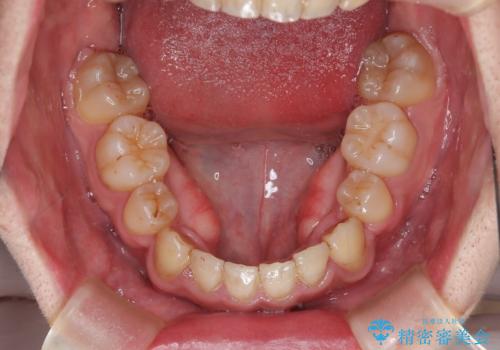

患者様にはかなり満足していただける結果となりました。

八重歯(3番)などは歯肉移植も検討できればよいかなと思います。

上顎は左右5番抜歯、下顎は左右4番抜歯しています。